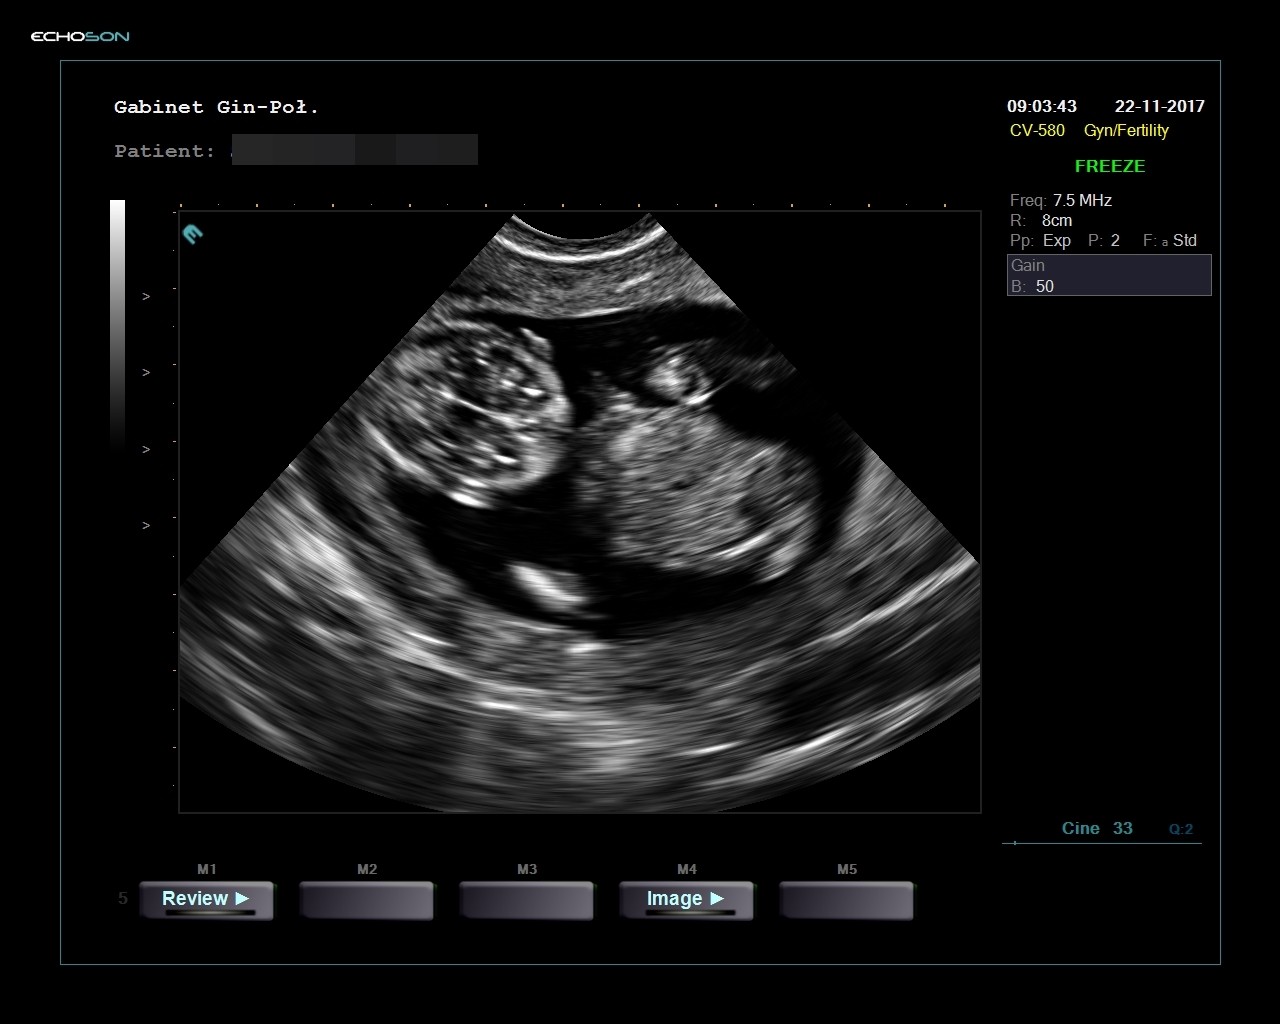

Przez powłoki można zobaczyć szyjkę, ale nie da się jej dokładnie zmierzyć. Dla zainteresowanych załączam link. Naprawdę warto o tym pamiętać bo wielu lekarzy zaniedbuje fakt mierzenia szyjki. Leżałam w szpitalu z porodem zagrażającym i naprawdę mnóstwo tam było dziewczyn z tym problemem.Ale widać że przez usg przez powłoki brzuszne też można to sprawdzić bo mój lekarz sprawdził i mam łożysko bardzo nisko nas szyjka

Też uważam, że trzeba o tym pamiętać i prosić. W holandii nie sprawdzają szyjki. W drugiej ciąży miałam usg połówowe w poniedziałek i nikt nic nie widział a w piątek rodziłam synka, który w 20 tyg nie miał najmniejszych szans przeżyć.Przez powłoki można zobaczyć szyjkę, ale nie da się jej dokładnie zmierzyć. Dla zainteresowanych załączam link. Naprawdę warto o tym pamiętać bo wielu lekarzy zaniedbuje fakt mierzenia szyjki. Leżałam w szpitalu z porodem zagrażającym i naprawdę mnóstwo tam było dziewczyn z tym problemem.

Link do: USG szyjki macicy